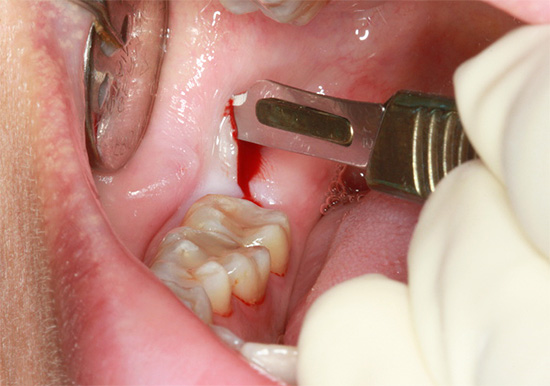

O principal significado da “complexidade” da remoção é pré-preparar o dente e, mais frequentemente, suas raízes, para extração com pinças ou elevadores. Para fazer isso, a parte da gengiva é excisada e o volume do tecido ósseo do orifício ao redor do dente é reduzido ou as raízes são separadas. Para esses fins, atualmente é usada uma broca com um conjunto de brocas especiais, além de vários instrumentos cirúrgicos adicionais.

Depois de cortar as gengivas, separar as raízes com uma broca e extraí-las do buraco, o buraco é limpo de “sujeira”: resíduos de ossos, pedaços de dentes cariados, resíduos de raízes, serragem. Para fazer isso, as bordas afiadas do buraco são suavizadas com pinças de osso ou uma broca, a ferida é lavada com soluções anti-sépticas, um medicamento é colocado no buraco (de acordo com as indicações) e as bordas da ferida são suturadas. Recomendações são dadas ou é marcado um acompanhamento para monitorar a qualidade da cura.